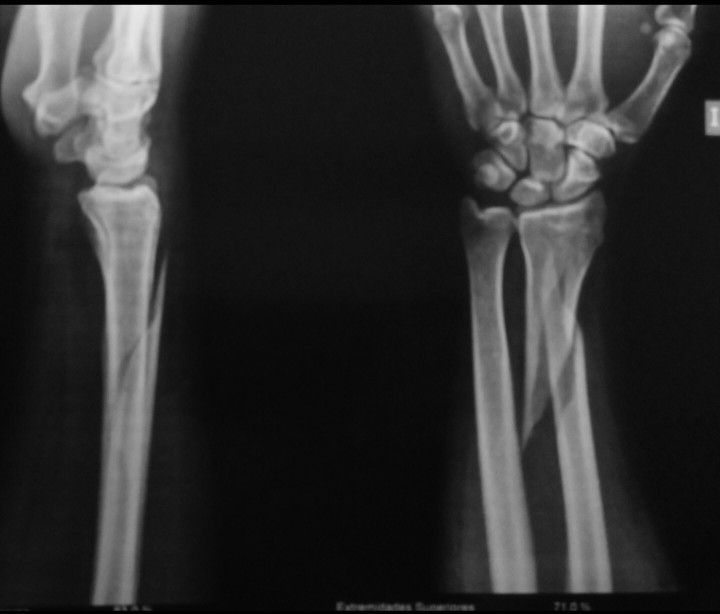

Уважаемые коллеги, прошу совета по погружному остеосинтезу перелома

лучевой кости.

Пациент: здоровый мужчина, слегка повышенного питания.